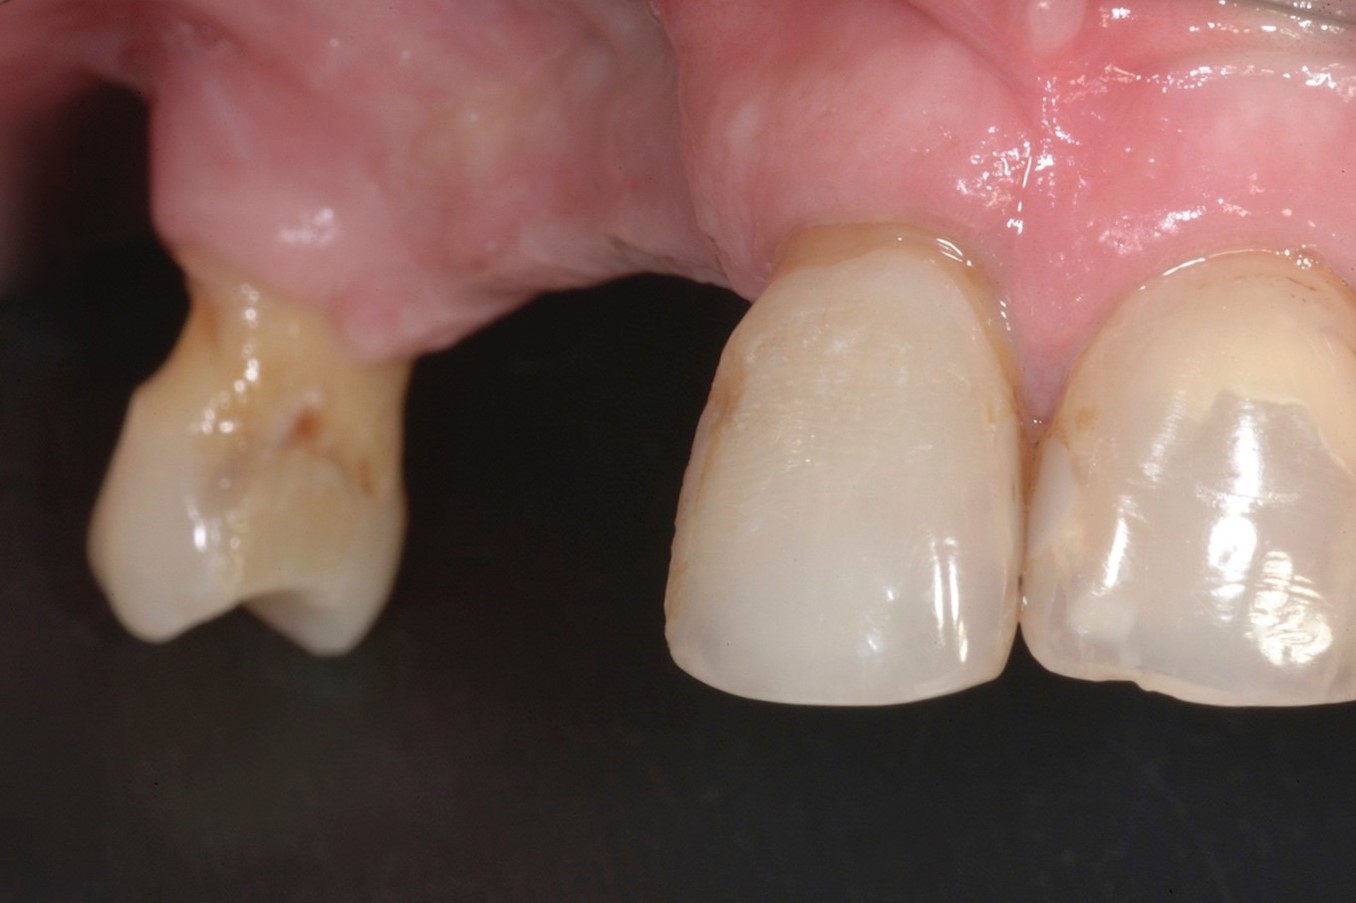

Fig 2. Preoperative view of a female patient who presented with a large defect.

Figure 2